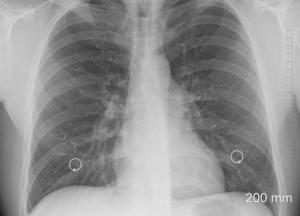

Медики перечислили пять симптомов рака легких

Типичные симптомы онкологии легких – это постоянный кашель, одышка и усталость, однако заболевание может проявляться и по-другому, передает FaceNews.ua.

Постоянные инфекции – еще один признак возможной онкологии. Как известно, многие вирусы проникают в организм через легкие, поэтому повторяющиеся инфекции грудной клетки должны насторожить.